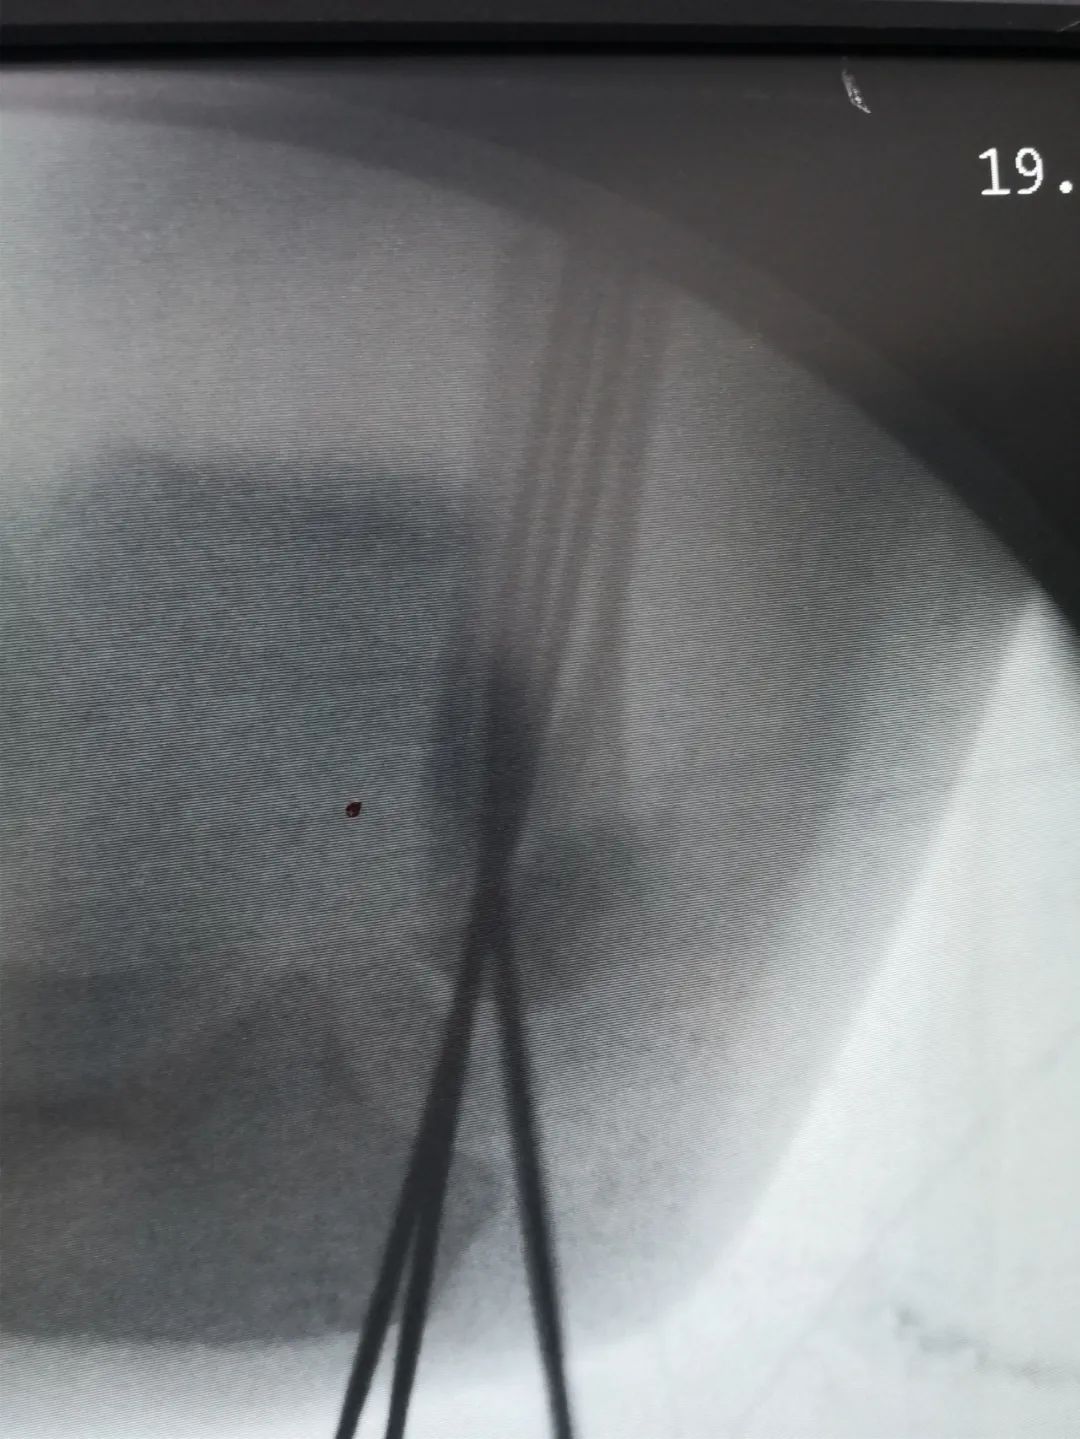

“对于另外2例骨折患儿,因未造成神经损伤,给予C臂透视下手法复位闭合穿针内固定手术,不用切口,创伤小,恢复快,术后四周门诊拔出钢钉,免除二次手术取内固定。”刘医生说道。